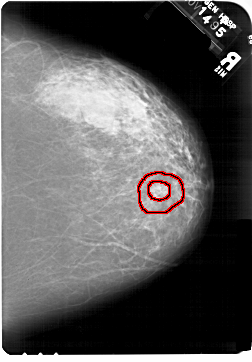

A_1467_1.RIGHT_CC

RIGHT_CC LINES 6871 PIXELS_PER_LINE 4786 BITS_PER_PIXEL 12 RESOLUTION 43.5 OVERLAY

FILE: A_1467_1.RIGHT_CC.OVERLAY

TOTAL_ABNORMALITIES 1

ABNORMALITY 1

LESION_TYPE MASS SHAPE ARCHITECTURAL_DISTORTION MARGINS SPICULATED

ASSESSMENT 5

SUBTLETY 1

PATHOLOGY MALIGNANT

TOTAL_OUTLINES 2

BOUNDARY

CORE